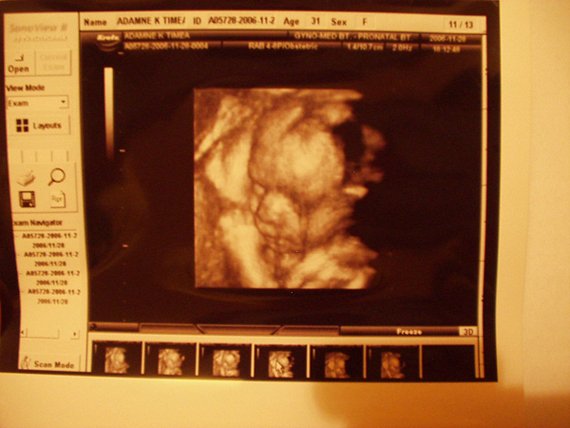

Mazsola: üdv itt megint köztünk! Gratula a babához! Én a második terhességemmel pont 25hetesen voltam 4D-n uh-n, de mivel nekem nagy volt a picurom, ezért nem lehetett egészben látni, csak részletekben, hogy éppen mit csinál a kislányom.

de igy is nagyon jó volt, most neked hány cm-t, és hány kg-ot saccolnak az uh-n?

Ha elvileg olyan súlyú mint az átlag babák, amiket irnak, hogy mennyi kell legyen a 25.héten, akkor szépen fogod látni, ha nagyobb, akkor már nem fér bele a képernyőbe teljesen, csak részletekben, mint a lányom.